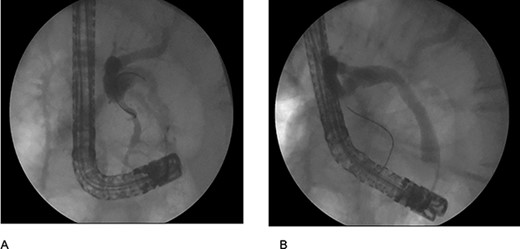

The patient was staged as ‘high risk’ according to the 2019 guidelines of American Society for Gastrointestinal Endoscopy risk classification guidelines for choledocholithiasis. The decision to perform an ERCP was taken, where an obstructive PDD was identified (Fig. 1). An absence of stones or biliary tumors was recognized (Fig. 2B) Oddi’s sphincterotomy and balloon sweep were performed, obtaining a control cholangiography without filling defects (Fig. 2). The initial presumptive diagnosis of choledocholithiasis was ruled out and a diagnosis of LS wasdone.

(A) duodenal diverticulum type C of Noda Classification; (B) bile duct deep cannulation; (C) sphincterotomy.